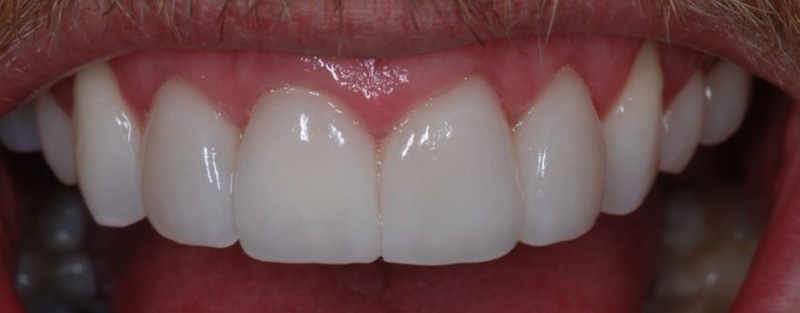

- Clinical: Cementing Veneers

- Clinical: Finishing Veneers